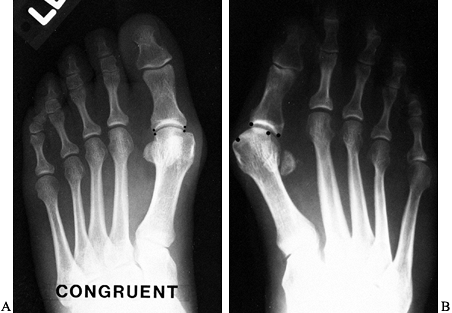

Figure 112.1. The normal hallux valgus (HV) angle is less than 15°; the intermetatarsal (IM) angle less than 8°. -

Look for arthrosis in the first

metatarsophalangeal joint and assess whether the joint is congruent or

incongruent. A congruent joint is one with no lateral deviation of the

proximal phalanx on the metatarsal head. An incongruent joint is one

with lateral deviation of the proximal phalanx on the metatarsal head (Fig. 112.2).

Figure 112.2. A:

A congruent metatarsophalangeal joint is one in which there is no

lateral subluxation of the proximal phalanx on the metatarsal head. B:

An incongruent metatarsophalangeal joint is one in which there is

lateral subluxation of the proximal phalanx on the metatarsal head. -